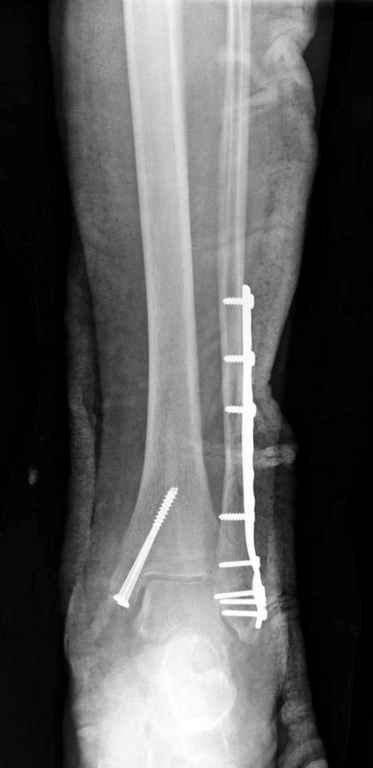

На 4-й неделе убрал спицы, с 7-й недели начал ЛФК, дозированную нагрузку, физиопроцедуры, массаж. Назначил хондропротекторы. Получилось вот что.

Rg-05.JPG

Удалены спицы, а гипса не было? 3-х лодыжечный перелом фиксировать 4 недели недостаточно. Что и подтверждается на последнем снимке - есть тенденция к подвывиху кнаружи, кзади... Что будет дальше, когда пациент начнет давать полную нагрузку?

Малоберцовая выглядит коротковатой. Профиль как-то мутный. Вообще, неплохо было бы сделать снимки в сравнении со здоровой.

Конечно, малоберцовая укорочена, надо сделать косой - мортиз снимок, тогда будеть понятно, на сколько.

Здесь финальный снимок 73 летней с

сопутствующей шизофренией, латерально бридж

пластину (соединили дистальный конец с диафизом не трогая место перелома) и медиально перкутанно

двумя шурупами. В этам случае без гипса не

обойтись.

Получился ожидаемый результат. Недостаточная длительность иммобилизации - подвывих, а жаль, первичная репозиция была замечательная, целесообразность назначения хондропротекторов, физиопроцедур вызывает сомнения.